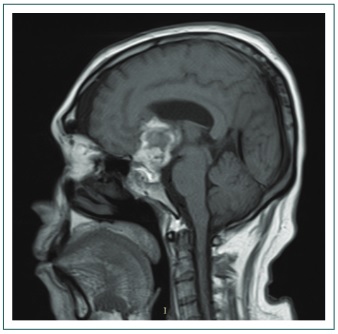

Un mes después reingresa por cefalea brusca de gran intensidad y rinorraquia, y es reintervenido con craniectomía para extirpación de tumor residual. Al segundo día de posoperatorio (Fig. 2) cursa con diuresis de 6000 ml/24 h, Na de 170 mEq/l y densidad urinaria de 1.002. Con diagnóstico de diabetes insípida central se inicia solución salina al 0.45%, 2400 ml/día, y desmopresina 20 μg/día por 5 días hasta la remission de la poliuria y Na de 144 mEq/l. Tras la suspensión de la desmopresina, el Na aumenta a 152 mEq/l, con una diuresis de 2800-3500 ml/día, por lo que se reinicia la desmopresina (20 μg/día) y el Na disminuye a 145 mEq/l, con una diuresis de 2000-2500 ml/día. Es dado de alta 4 días después con desmopresina 20 μg/día agregada a la terapia hormonal indicada.

Resonancia magnética cerebral, en T1, luego de la segunda cirugía.